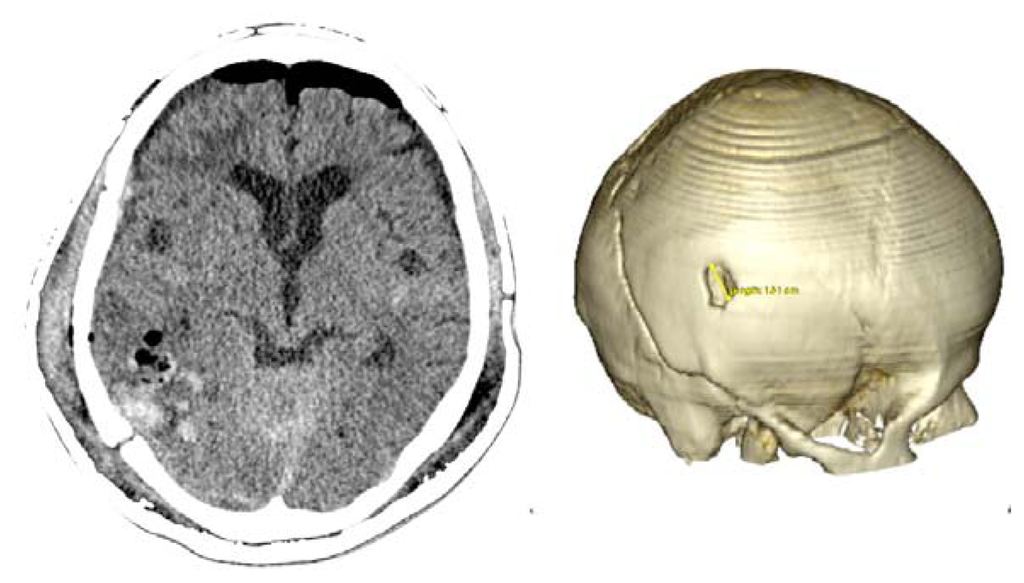

Case 2-Subdural Hematoma (See Figures 3 and 4 for the details)

A male patient of 44 years old was brought to the emergency department by relatives after falling from a height of 2 m. As the patient was well after the fall, he did not seek medical attention immediately. When he was admitted to the emergency room he presented GCS of 14 with left hemiparesis with muscle strength grade IV. The CT scan showed a subacute subdural hematoma extending over the entire convexity of the right brain. Therefore, he was promptly sent to the operating room. Upon completion of the 3D analysis it was opted for an endoscopic treatment of hematoma by a burr-hole positioned adjacent to the hematoma. The surgery was performed with no complications, and total resection was achieved. The patient had an excellent recovery, reversing the preoperative deficits. He was discharged four days after hospital admission.